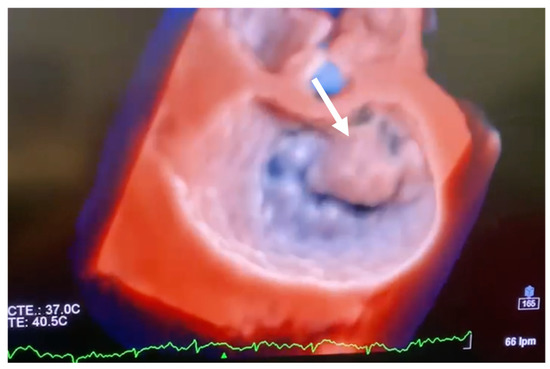

5. Diagnosis